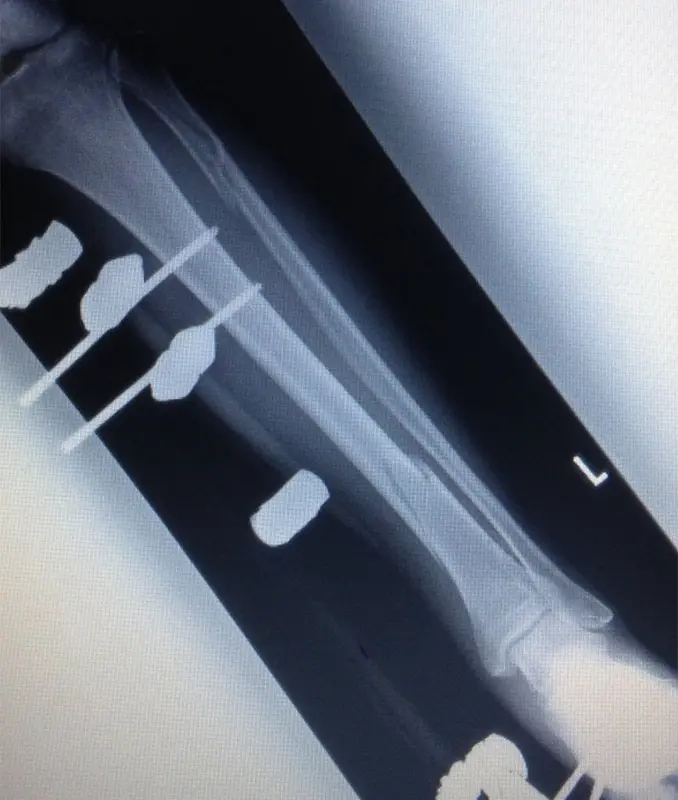

(図2)創外固定後単純X線